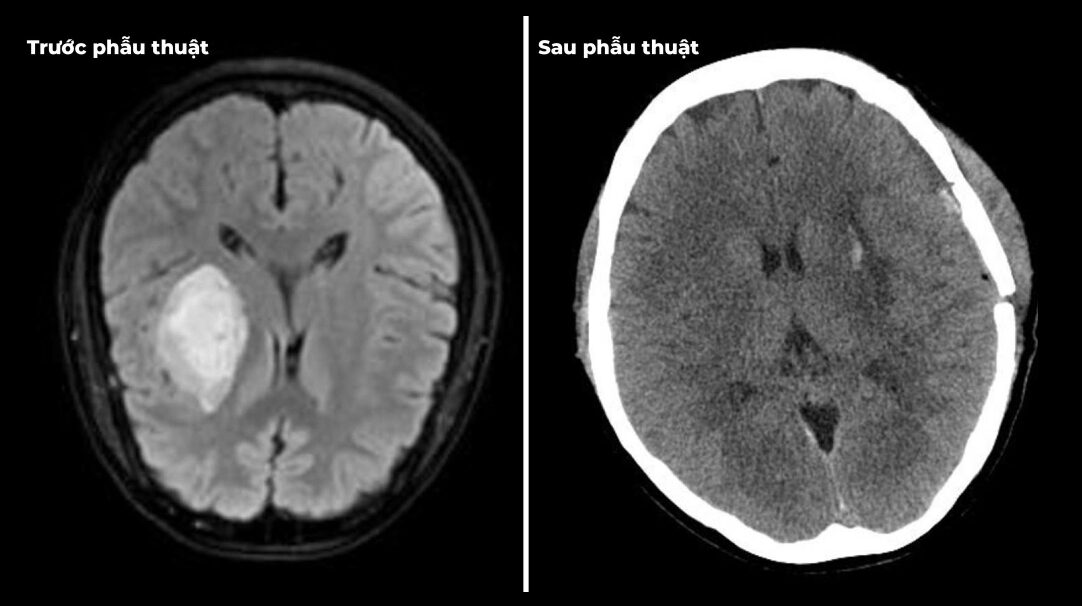

Thông tin từ Bệnh viện Đa khoa Hùng Vương cho biết, khi vào viện, cả hai bệnh nhân đều trong tình trạng nguy kịch, rối loạn ý thức, huyết áp cao kịch ngưỡng. Ngay lập tức, các bác sĩ đã khẩn trương cấp cứu, tiến hành phẫu thuật để kiểm soát tình trạng chảy máu não và giảm áp lực nội sọ. Nhờ can thiệp kịp thời, hiện tại các bệnh nhân đã qua cơn nguy hiểm. Tuy nhiên, di chứng để lại vẫn rất nặng nề, ảnh hưởng nghiêm trọng đến sức khỏe và chất lượng cuộc sống. Đây là hồi chuông cảnh báo về sự nguy hiểm của bệnh tăng huyết áp, đặc biệt ở người trẻ tuổi – nhóm đối tượng thường chủ quan, không kiểm tra huyết áp định kỳ.

Bác sĩ đã khẩn trương cấp cứu, tiến hành phẫu thuật để kiểm soát tình trạng chảy máu não và giảm áp lực nội sọ